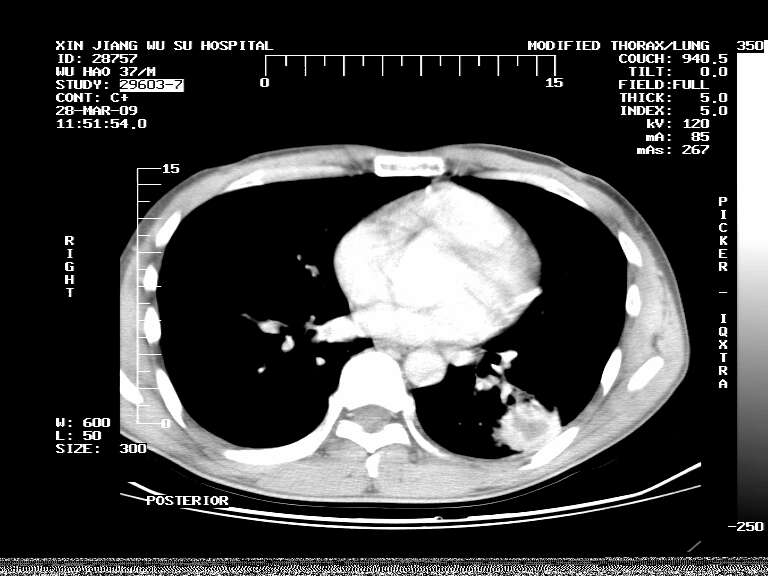

男,37岁,体检胸透发现阴影。

患者体检发现 无症状 左肺下叶占位,边缘模糊,可见血管聚束、分叶、胸膜牵拉,增强呈不均匀性强化。 首先考虑左肺下叶周围型肺癌,建议穿刺活检。

左肺下叶见一结节病变,边缘欠清不光滑,与胸膜粘连且胸膜局限性增厚,注药后呈环形强化,动脉期壁呈明显点环状强化,静脉期壁强化减低,中心密度低无强化,灶周无明显的卫星灶和水肿区(晕征)---考虑周围性肺癌,不除外感染性病变,建议穿刺活检。

周围有卫星灶,胸膜反应不明显,病灶中心有坏死。建议先抗结核治疗后,短期复查

左肺下叶大片实变影,内靠胸膜见不规则更高密度结节灶,边缘强化,相邻胸膜增厚,胸膜下脂肪线存在。考虑炎症,结核可能。